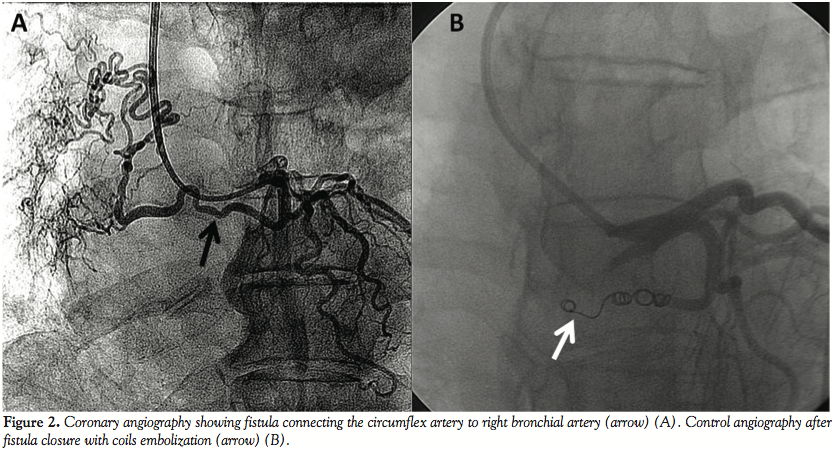

the pulmonary vasculature (Figure 1). Therefore, we performed coronary angiography, which depicted no coronary artery disease. However, it identified a fistula between the circumflex artery and right bronchial artery (Figure 2A). The fistula was successfully occluded at its proximal third with 3 coils (3 mm/3.3 mm + 4 mm/3.7 mm+ 5 mm/5.5 mm) (Figure 2B). The patient remained stable, with normal ECG and cardiac enzymes after 48 hours. At 1-month follow-up, the patient continued with the same complaint of angina. A new coronary angiography was performed. It showed no stenosis or induced coronary spasm and total occlusion of the fistula at its proximal third.